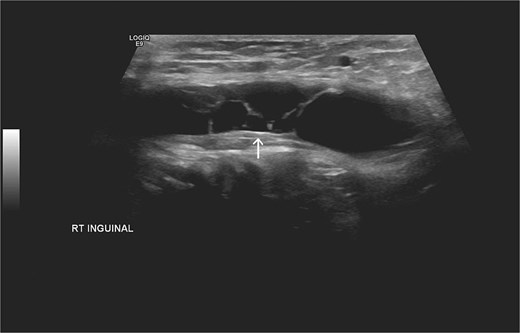

Laboratory studies, including complete blood count and comprehensive metabolic panel, were within normal limits. Initial ultrasonography (US) revealed an oblong cystic lesion with fine septations, measuring 6.5 × 3 cm, extending through the right inguinal canal into the labium majus (Figs 1 and 2). Subsequent pelvic magnetic resonance imaging (MRI) corroborated these findings, demonstrating a right lower abdominal cystic lesion with thin septations extending to the inguinal region, showing low T1 and high T2 signal intensity, measuring ~7 × 3.5 cm (Figs 3 and 4). No evidence of bowel or omental herniation was observed, suggesting canal of Nuck hydrocele.

Additional US of the right inguinal area showing fine internal septations of the lesion as indicated by the arrow.